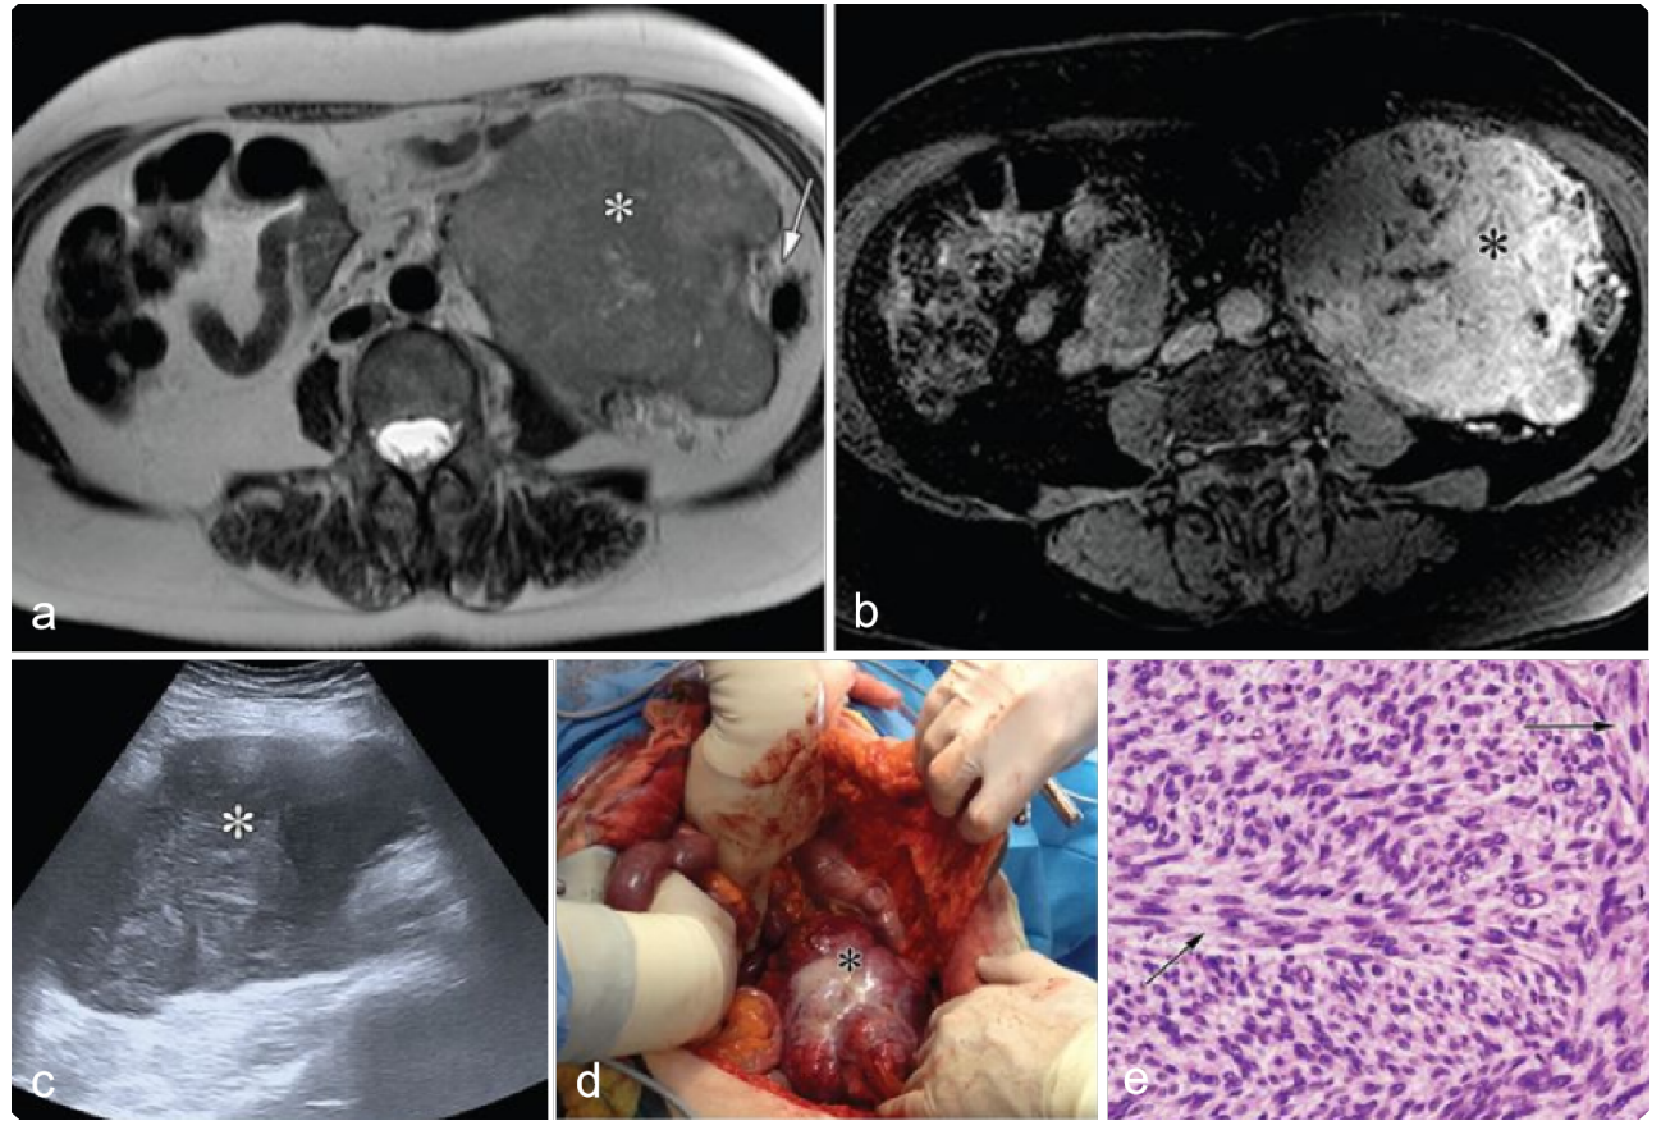

腹膜后及腹腔内副交感神经节瘤亦称非嗜铬性副交感神经节瘤,肿瘤常位于腹主动脉旁或其分叉处,通常较大,常有包膜,包膜上有弯曲粗大的血管,约1/3可转移至肺、肝肾上腺等处。副神经节瘤可同时伴发胃平滑肌肉瘤和肺软骨瘤。

副神经节瘤多呈囊实性肿块,坏死较多者,形成多囊样改变,并可见分隔,强化显著且持续时间较长,病灶周围或瘤内可见粗大强化的血管影及分隔样结构。副神经节瘤具有特征性MR表现,T2WI呈显著高信号,且肿瘤具有血管样显著强化。

a9dd1b7b60ddae31b2682e3a433c993e.png 病例 41:(左侧腹膜后)副神经节瘤1例20%的腹膜后副神经节瘤发生在肾上腺外,来源于脊椎旁交感神经链;大部分形态较规则,边界清楚,由于供血不均,部分容易坏死、出血、钙化和囊变,血供主富,增强后强化显著,可见肿瘤血管,呈早期、进行性延迟强化。

11b77622e265a21ed90c136aff4489c2.png 病例 42:左侧腹膜后副神经节瘤  62岁女性左侧腹膜后大肿块,边界不清,密度明显不均匀,内可见囊性坏死区及粗钙化灶,增强扫描可见实变区明显强化,中心囊性区未见强化。

876c932d97c9df698f0d9b0c2123d636.png 病例 44:(腹膜后)副神经节瘤  47岁女性,体重减轻、腹痛和坐骨神经痛(a) 增强CT图像显示主动脉分叉水平肿块,中央坏死(*)和外周明显强化 (箭)。(b, c) T2WI及T1WI+C显示中央高信号坏死区(*)和明显的周边强化。(d) 大体病理显示边界清楚的包裹性肿块,病灶中央有粘液样和凝胶状成分(*),周围有红色出血(**)和黄色坏死区(箭头)。大口径血管(肠系膜下动脉)被肿瘤完全闭塞(箭)。(e) 镜下显示典型的zellballen生长模式,肿瘤细胞巢(*)被纤维血管隔 (箭头) 包围(HE×40)。(f) 高倍镜下显示嗜酸性粒细胞的细胞质、具有核仁的中央核和核内假包涵体(箭头)(HE×400)。